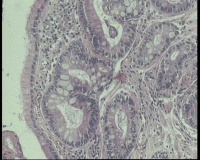

请老师看看胃角溃疡,上皮有轻度非典型增生吗?

性别年龄58岁临床诊断胃角溃疡

一般病史胃角:近后壁见一处圆形溃疡,大小0.6x0.6厘米,底附黄白苔,周围粘膜充血水肿

标本名称胃镜活检

大体所见胃镜活检组织

镜下胃粘膜腺体肠化,局灶腺上皮细胞核大

有坏组织,符合溃疡,腺体肠化,轻度不典型增生。

溃疡+萎缩+肠化+修复。

有肠化和修复性增生。